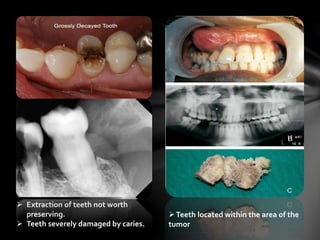

Teeth located within the area of the

tumor

 Extraction of teeth not worth

preserving.

 Teeth severely damaged by caries.